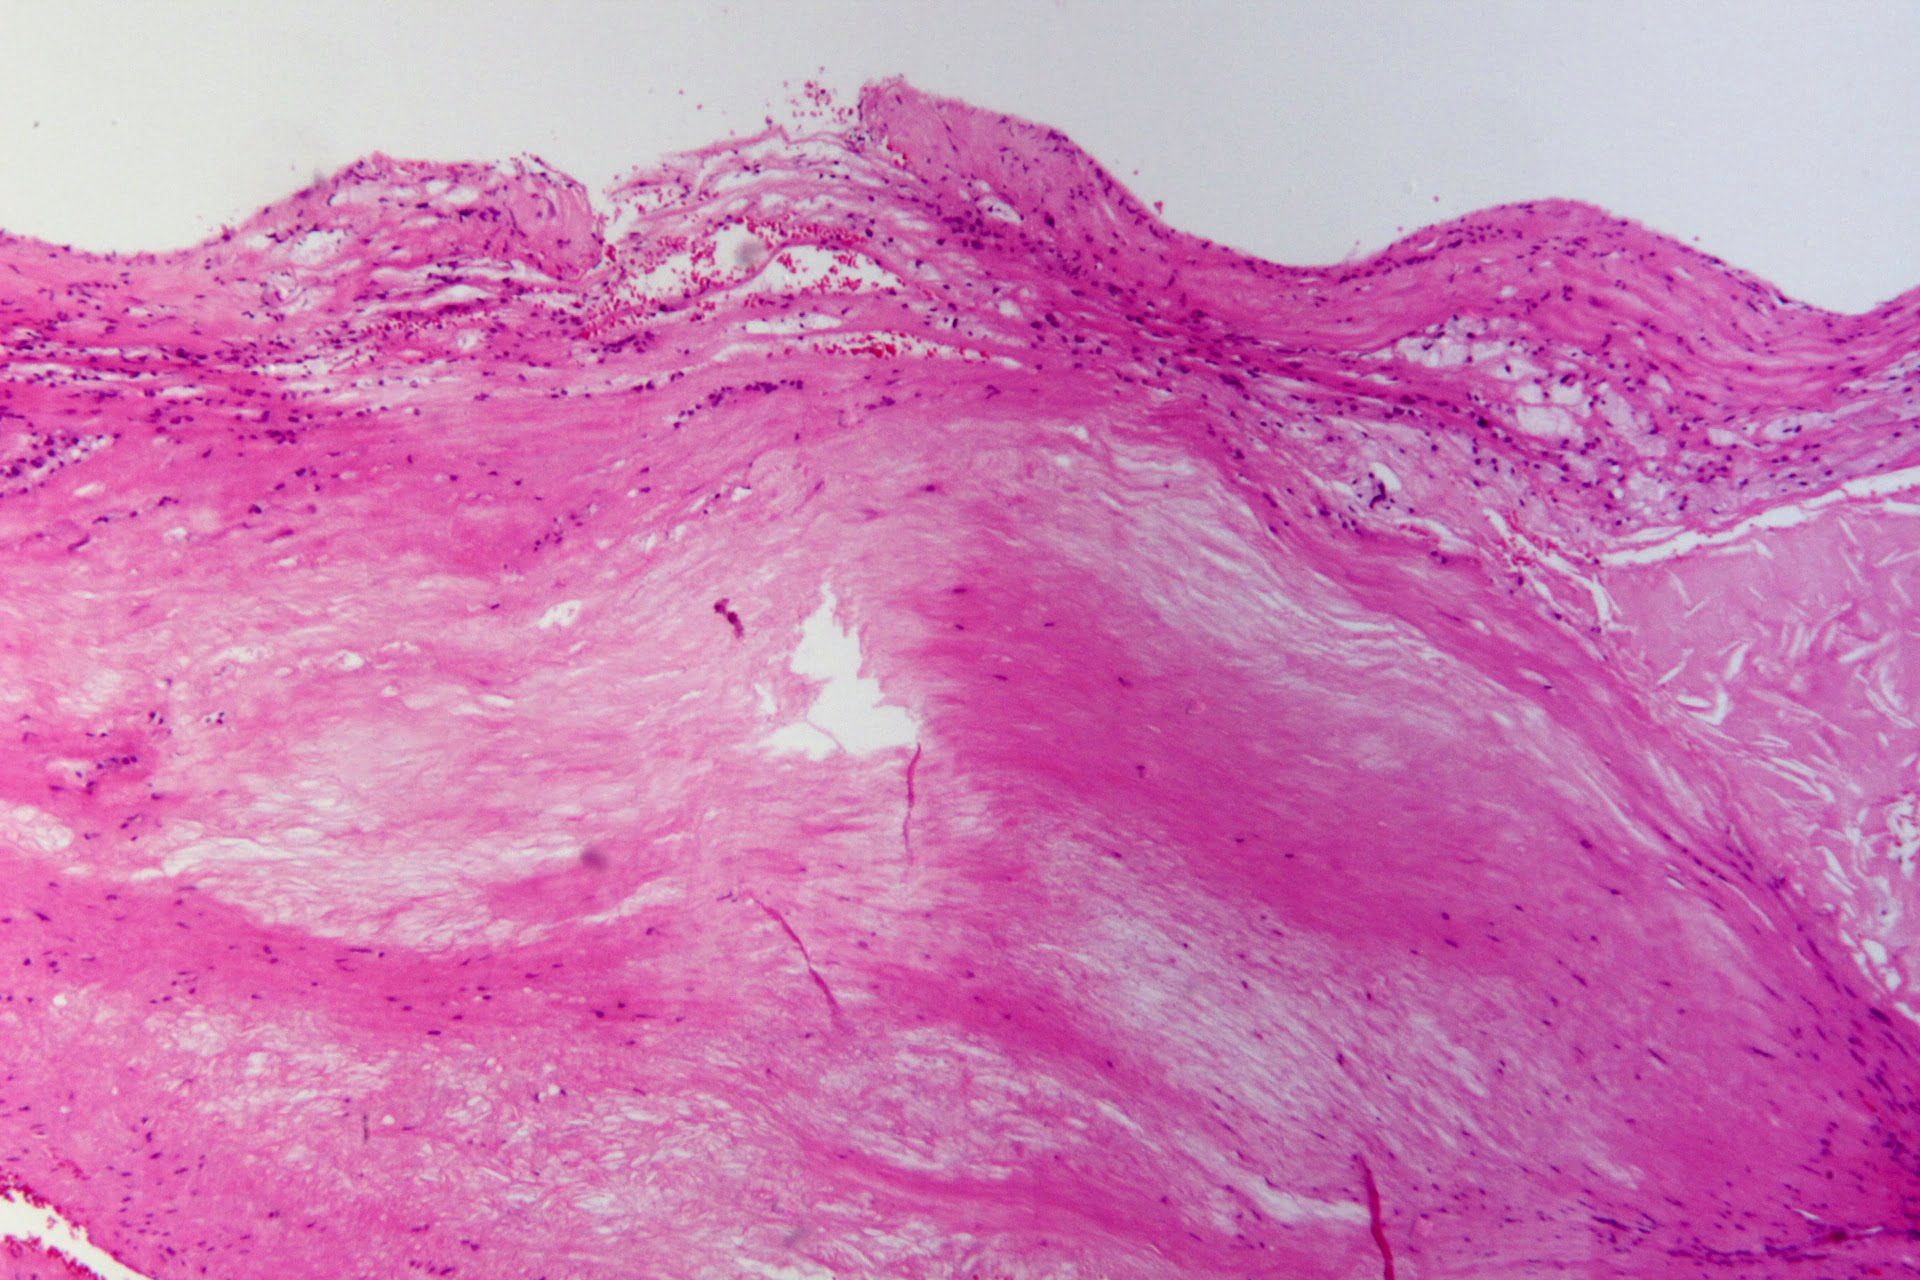

Ateroscleroza este o boala caracterizata prin formarea de ,,placi galbui” (din depunerea de grasimi si cristale de colesterol) pe peretii arterelor mijlocii si mari, si care poate duce la astuparea vasului sau la rupturi ale peretilor acestora.

Ateroscleroza are o consecinta grava – reducerea diametrului arterelor (ingustarea lumenului vascular) si astfel reducerea cantitatii de sange (care iriga diferite organe si tesuturi), proces numit ,,ischemie”. Factorii care favorizeaza dezvoltarea aterosclerozei, sunt: modul de viata al oamenilor, obiceiurile alimentare, apa potabila, aerul, modul pasiv de viata si solicitarea psihica. In prezent, bolile cardio-vasculare sunt foarte raspandite.